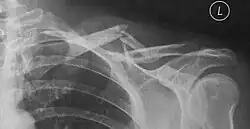

Häufig ergibt sich schon bei der klinischen Untersuchung die Diagnose durch lokale Schwellung, Druckschmerz, tastbare Knochenenden unter der Haut oder Knochenreiben (Krepitation). Die Diagnose wird durch eine Röntgenuntersuchung bestätigt.

Unabhängig davon, ob die Ruhigstellung mit einer Schlinge oder mit Rucksackverband erfolgt, wird oft eine wöchentliche radiologische Verlaufskontrolle – durch Röntgenbilder – während der gesamten Behandlungsdauer von 6 Wochen empfohlen, da vor allem bei Klavikulafrakturen des mittleren Drittels noch deutliche Verschiebungen der Knochenfragmente auftreten können, was dann operativ versorgt werden kann.[15][11]